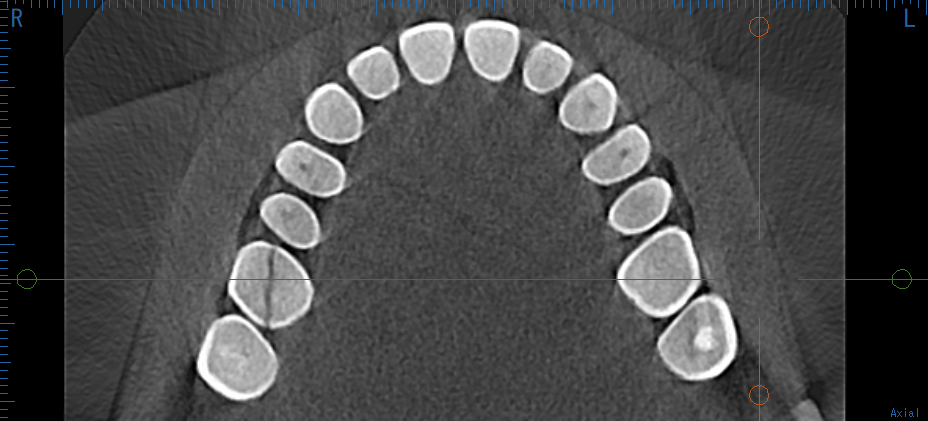

これは私のCT画像です。上の6番目の歯が真っ二つに割れています。

根まで割れているので抜歯です。歯を残すことは不可能でした。